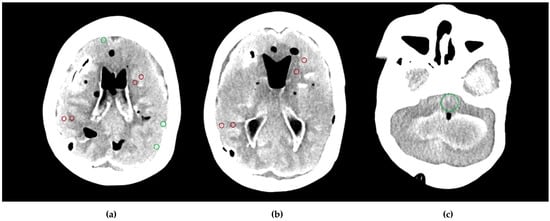

Quantitative assessment of image quality followed the same methodology as described in the phantom study (Section 2.1.2). The exception in the patient study was fixed ROIs at three pairs of identical GM and WM locations in the frontal and parietal lobes and in the thalamus and adjacent posterior limb of the internal capsule, while SCA and PFAI were measured once at the level of the midbrain and near the skull, respectively (Figure 4).

Figure 4.

Placement of the region of interest (ROI) on the patient’s cross-sectional image data at gray matter–white matter pairs in (a) the frontal and parietal lobes, the thalamus, and the posterior limb of the internal capsule; (b) the posterior fossa; (c) the subcalvarial region.